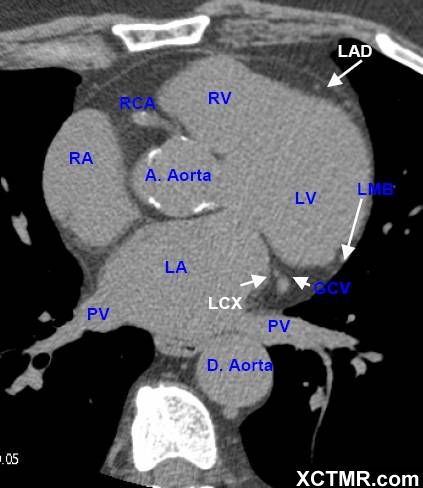

LA - Left Atrium 左心房

RA - Right Atrium 右心房

LV - Left Ventricle 左心室

RV - Right Ventricle 右心室

A. Aorta-Ascending Aorta 升主动脉

D. Aorta-Descending Aorta 降主动脉

PV - Pulmonary Vein 肺静脉

LAD - Left Anterior Descending Artery 左前降支

LCX - Left Circumflex Artery 左回旋支

LMB - Left Obtuse Marginal Branch 左边缘支(钝缘支)

GCV –Great Cardiac Vein 心大静脉